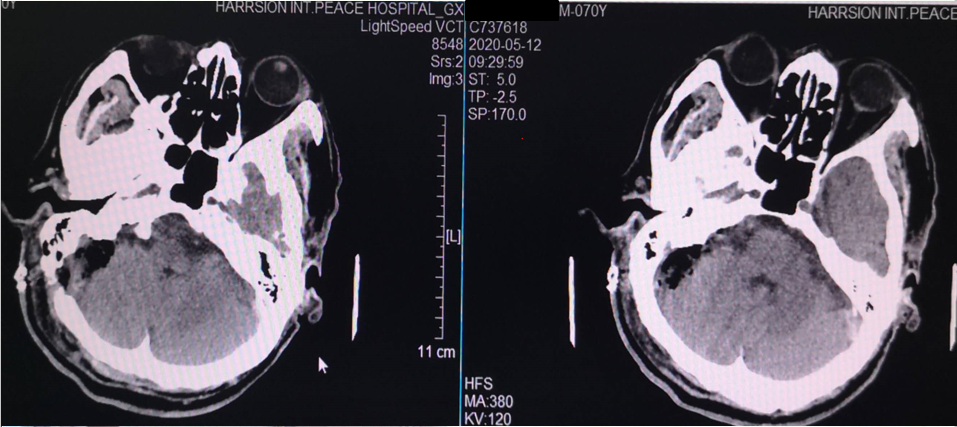

术后复查CT

69岁,女性。左侧面部及舌头疼痛10年,加重半年。张口、说话、咀嚼时明显加重伴有舌部(包括舌前2/3及舌后1/3)疼痛。

MRI示:左侧三叉神经与岩静脉关系密切,左侧后组颅神经与小脑后下动脉关系密切。